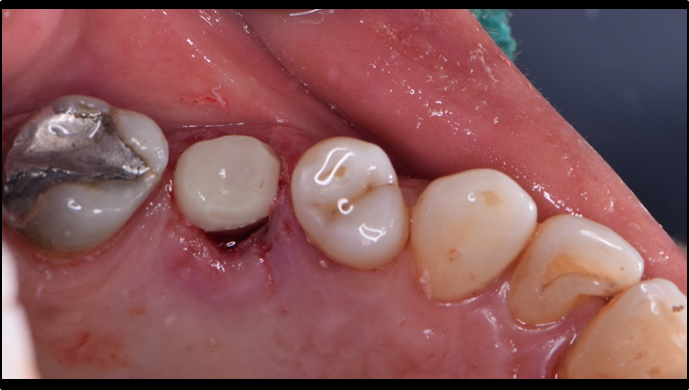

“Does guided surgery always mean flapless surgery? ”

Clinical case: R2GATE GUIDE surgery with GBR

- Courtesy of Dr. Kwang Bum Park, Korea -

Dr. Kwang Bum Park, digital guided surgery, bone regeneration, maxillary posterior, #13, #14, guided surgery, GBR, AnyRidge, i-GEN, Mega-Oss, R2GATE, R2GATE Full surgical kit